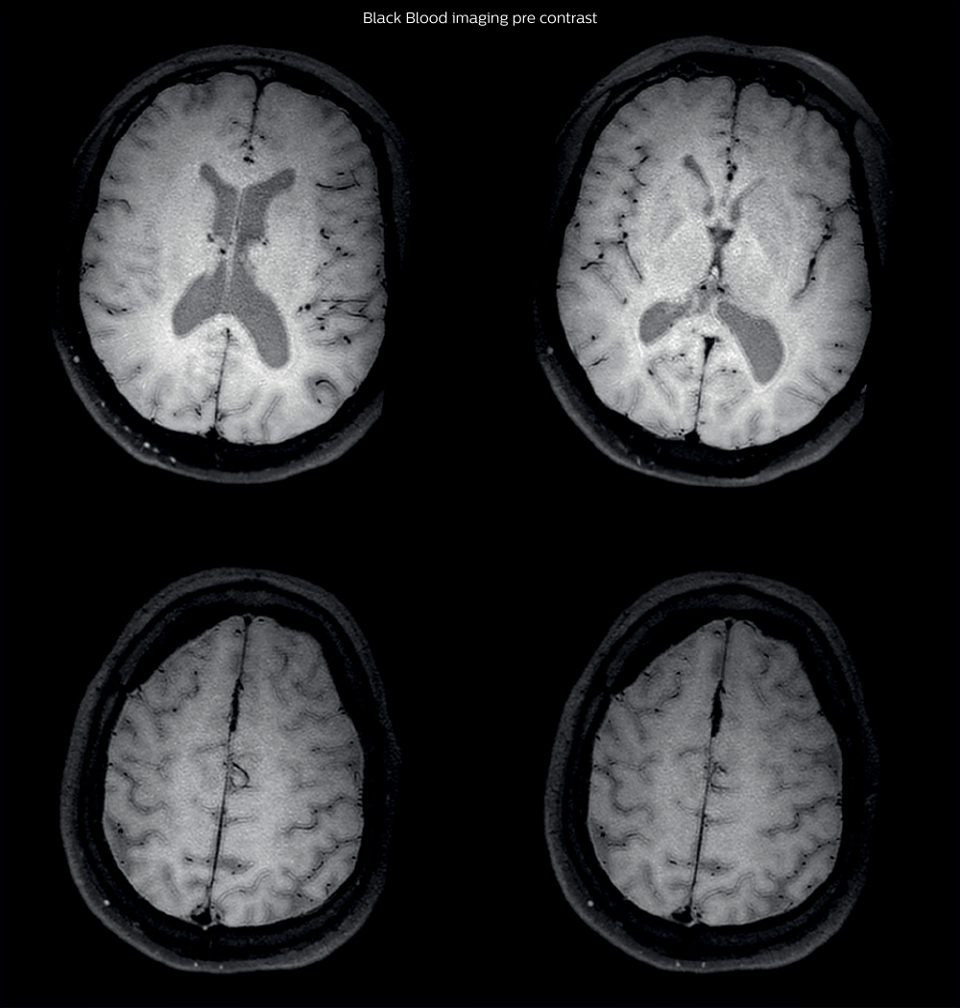

On FLAIR images we can see some nonspecific high signal abnormalities in frontal white matter bilaterally. On DWI we can see acute ischemic lesions which appear with high signal intensity. Arrows show vessel wall enhancement which appears concentric and homogeneous in different cerebral territories.

Black Blood Imaging Case 1 B Pre contrast1

On the routine MR sequences that we did, we could see acute

ischemic lesions. We see them very well on the diffusion images,

where acute ischemic lesions usually appear with high signal

intensity and restricted diffusion. However, the etiology of these

lesions cannot be derived from these images.

An area of restricted diffusion was seen in the anterior cerebral

artery territory and we concluded it was an ischemic lesion. On

MR angiography we can just see if there is stenosis or vessel

occlusion, but it does not provide us information on the etiology

of this kind of lesion.